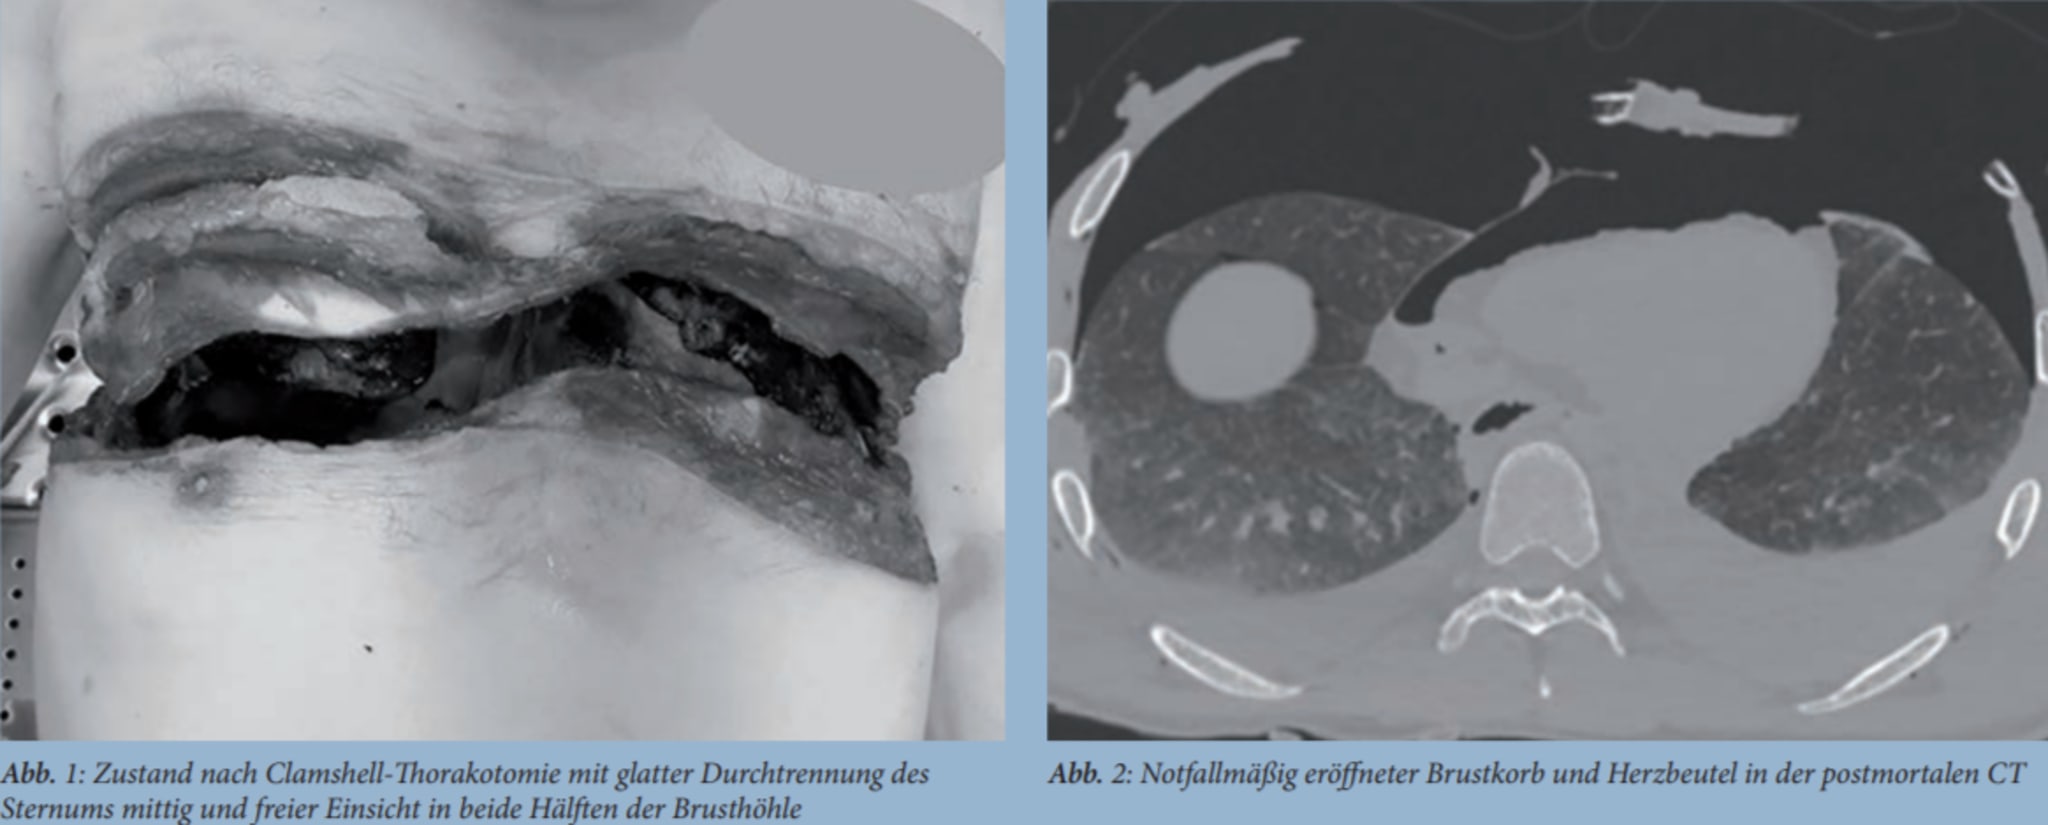

Maximalinvasive Reanimation mittels ClamshellThorakotomie coliquio Ed Clamshell Thoracotomy I have seen both left lateral and clamshell approaches and am convinced that clamshell offers significant advantages. Resuscitative thoracotomy is a thoracotomy performed prehospital, in the emergency department or elsewhere that is an integral part of the initial resuscitation of a. Check out our downloadable procedure card with qr code link to the. Release of cardiac tamponade [2] [3] for. Ed Clamshell Thoracotomy.